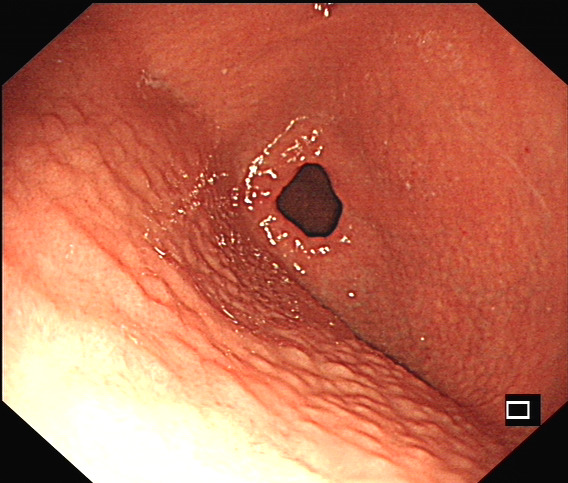

幽门螺旋杆菌感染临床上颇为常见,本次查看体检结果,发现一个“珍珠胃”的,其实就是胃窦结节样改变,这个是幽门螺旋杆菌感染内镜下最典型的一个表现了,其他的还有粘膜发红充血、息肉等,相对来说缺乏一些特异性。

幽门螺旋杆菌感染相关胃炎胃镜下表现